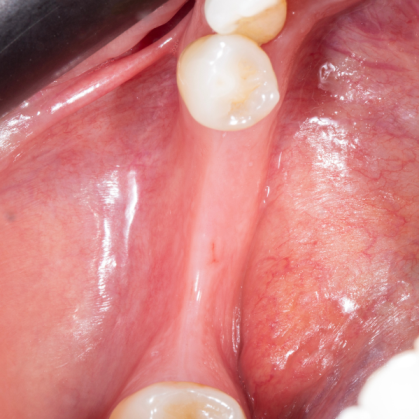

Diş çekiminin yıllar önce yapılmış olmasına bağlı olarak ince kemik varlığında implant ve kemik grefti uygulandı